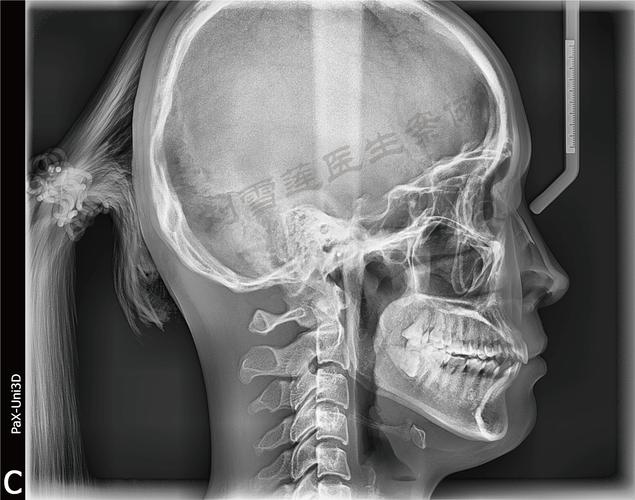

拍摄头颅侧位片需严格遵循标准化流程,以确保图像的准确性和可重复性,患者通常取站立位或坐位,头部自然放松,眶耳平面(外耳道上缘与眼眶下缘的连线)与地面平行,矢状面(通过鼻根和枕骨外粗隆的平面)与地面垂直,避免头部倾斜或旋转,X线球管中心线对准外耳道上方5cm处,拍摄距离一般为1.5-2米,以减少图像放大失真,儿童患者需配合固定装置(如头颅固定架)防止移动,必要时在家长协助下完成,整个拍摄过程快速、无创,辐射剂量极低(约0.007mSv),相当于乘坐飞机2小时所受的宇宙辐射,安全性高。

头颅侧位片的准确性依赖于拍摄标准化,任何头部倾斜、旋转均会导致测量误差,需由专业技师操作,对于生长发育期儿童,需结合手腕骨龄片评估生长潜力,头颅侧位片可定期拍摄(如每6-12个月)以监测骨骼变化,头颅侧位片需与全景片(观察牙根、牙槽骨)、口腔模型(分析牙弓形态)等联合应用,实现多维度评估,避免单一检查的局限性。